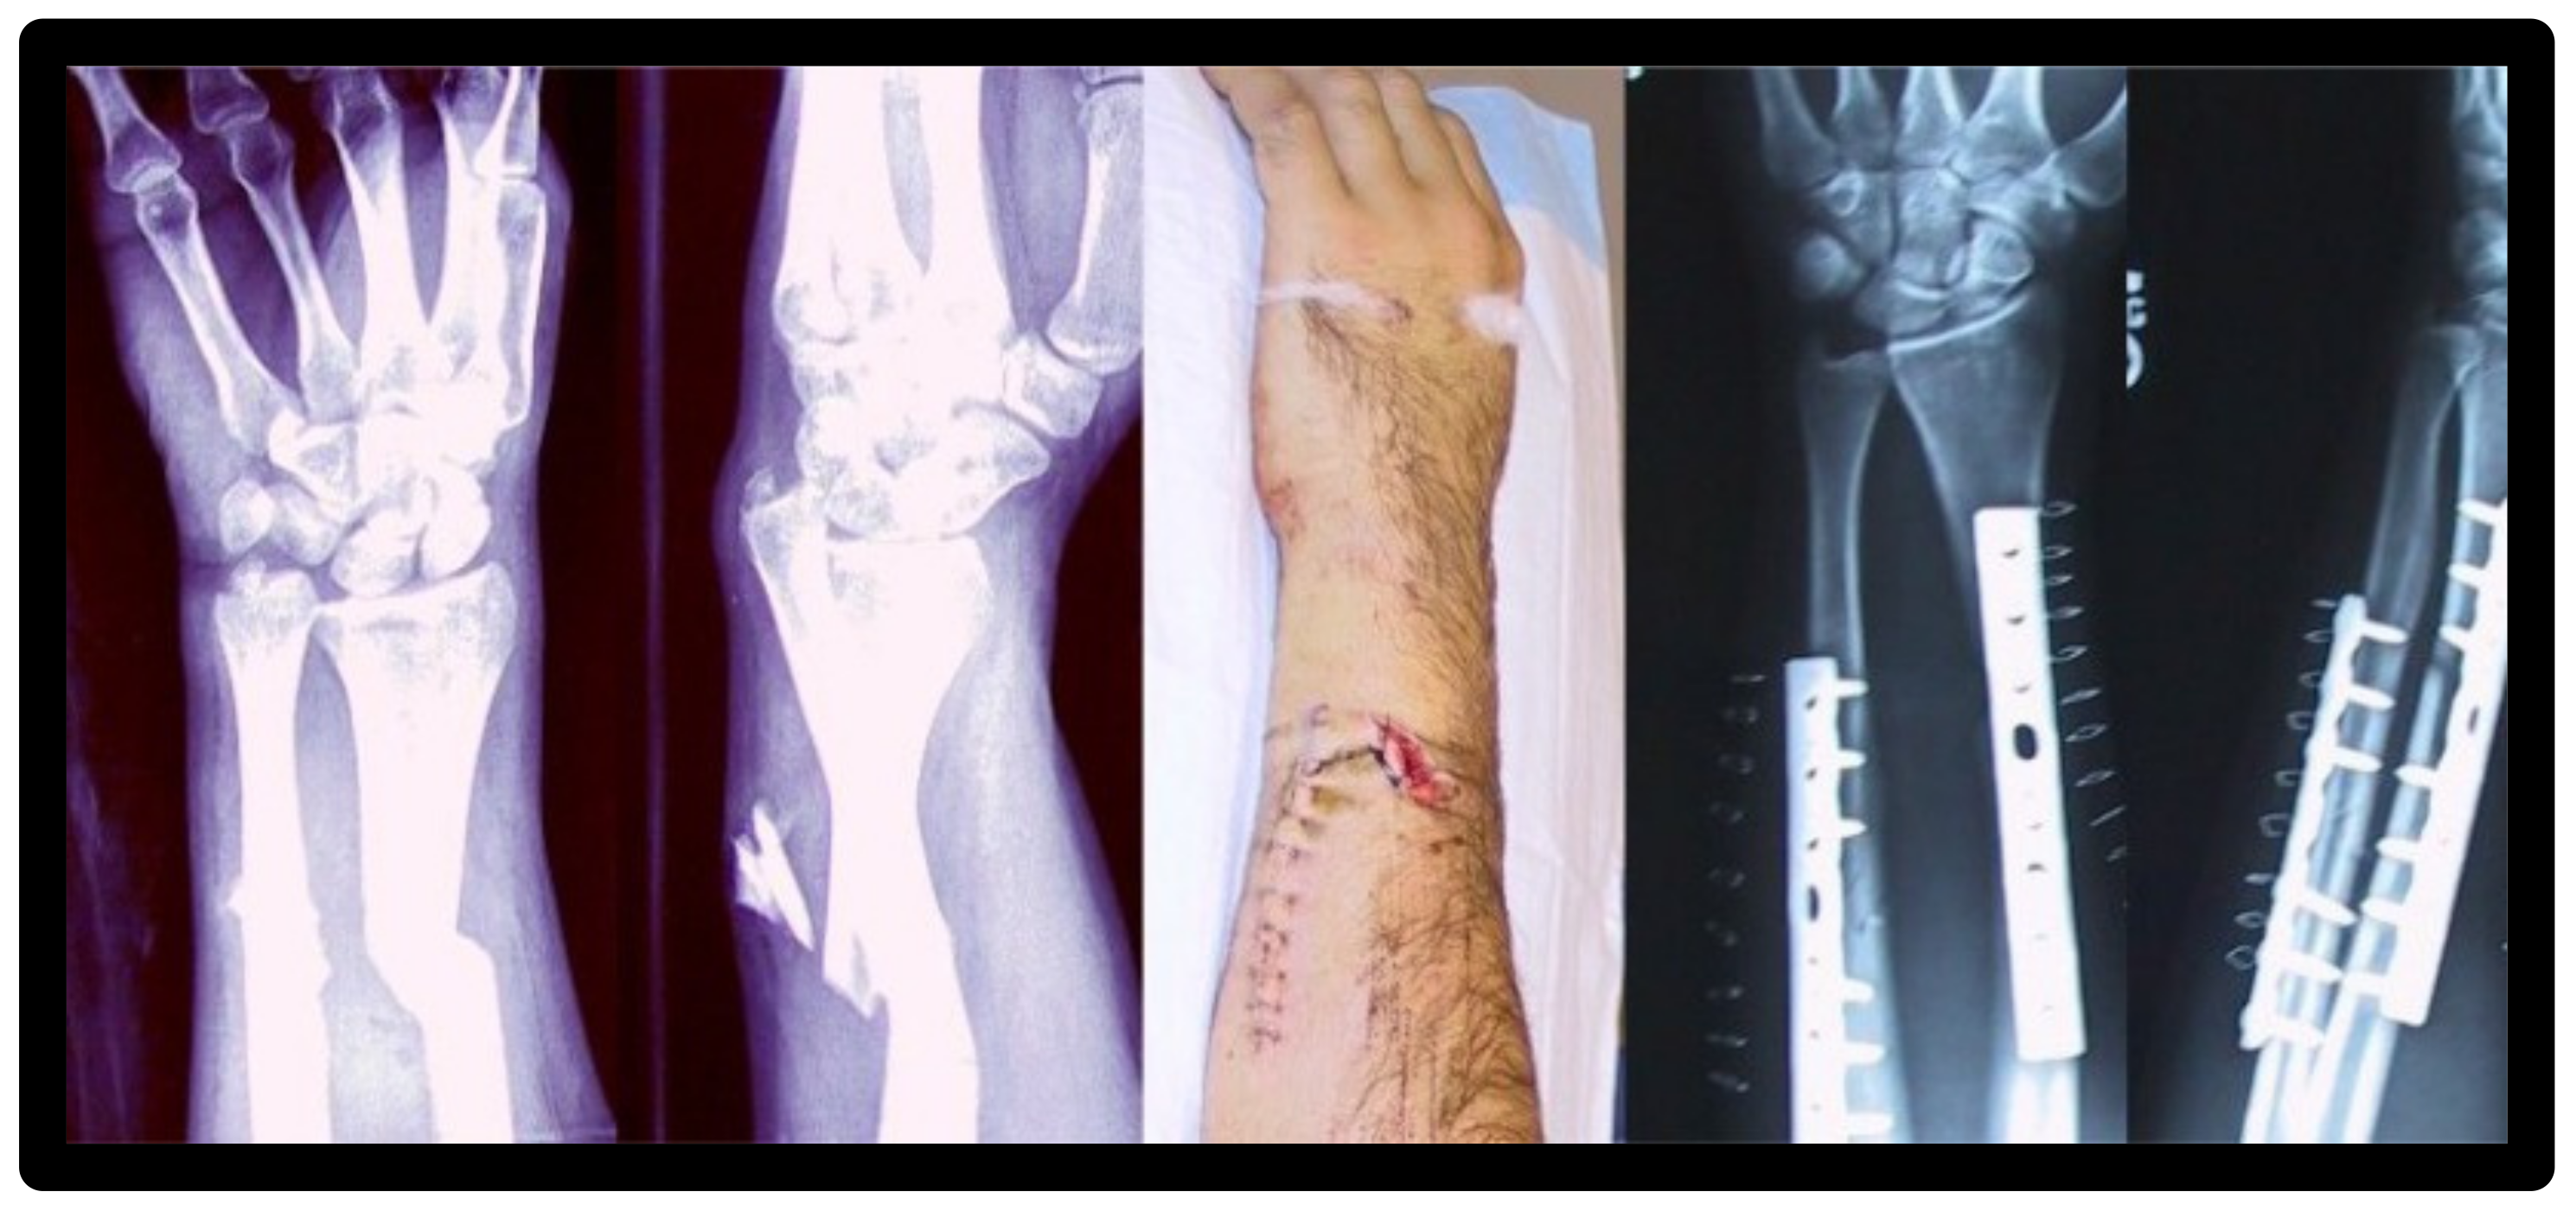

- Roth, A.K.; Karlien Boon-Ceelen; Smelt, H.; Bert van Rietbergen; Willems, P.; Rhijn, van; Arts, J.J. Radiopaque UHMWPE Sublaminar Cables for Spinal Deformity Correction: Preclinical Mechanical and Radiopacifier Leaching Assessment. Journal of Biomedical Materials Research Part B 2017, 106 (2), 771–779. [CrossRef]

- Bogie, R.; Roth, A.K.; Faber, S.; Jong; T. Welting; Willems, P.; Arts, J.J.; L.W. van Rhijn. Novel Radiopaque Ultrahigh Molecular Weight Polyethylene Sublaminar Wires in a Growth-Guidance System for the Treatment of Early-Onset Scoliosis. Spine 2014, 39 (25), E1503–E1509. [CrossRef]

- Kozakiewicz, M.; Leszek Olbrzymek; Ludomir Stefanczyk; Marek Olszycki; Komorowski, P.; Walkowiak, B.; Konieczny, B.; Krasowski, M.; Jerzy Sokołowski. Radio-Opaque Polyethylene for Personalized Craniomaxillofacial Implants. Clinical oral investigations 2016, 21 (5), 1853–1859. [CrossRef]